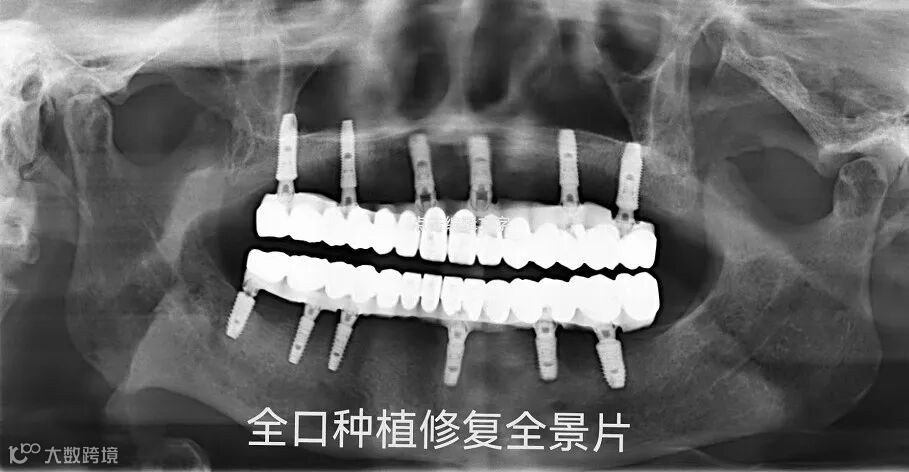

- 案例① -

牙齿美容性修复